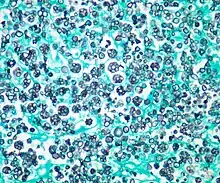

Histologic stain of a Prototheca zopfii infection in a dog